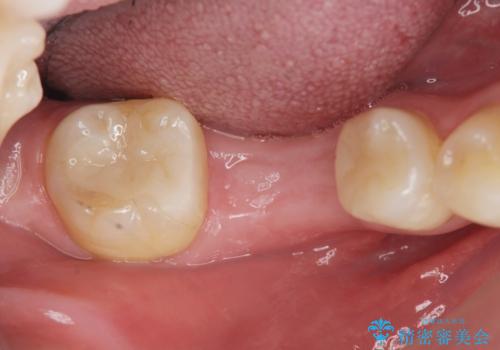

失った歯のインプラント補綴

- 歯の破折により失ってしまった右下の歯の機能回復を求めて来院されました。

取り外しの必要な入れ歯や、歯を大きく削る必要のあるブリッジではなく、インプラント治療を希望されました。